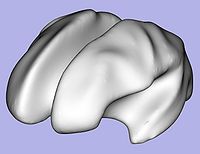

- 1.7. Genus zero cortical surface creation and inflation

- 1.7.1. Genus zero cortical image and surface creation

- Tool: GenusZeroImageFilter (UNC Slicer3 external module)

- 1.7.2. White matter surface inflation

- Iterative smoothing using relaxation operator (considering average vertex) and L2 norm of the mean curvature as a stopping criterion

- Iteration stopped if vertices that have too high curvature (some extremities)

- Tool: MeshInflation (UNC Slicer3 external module)